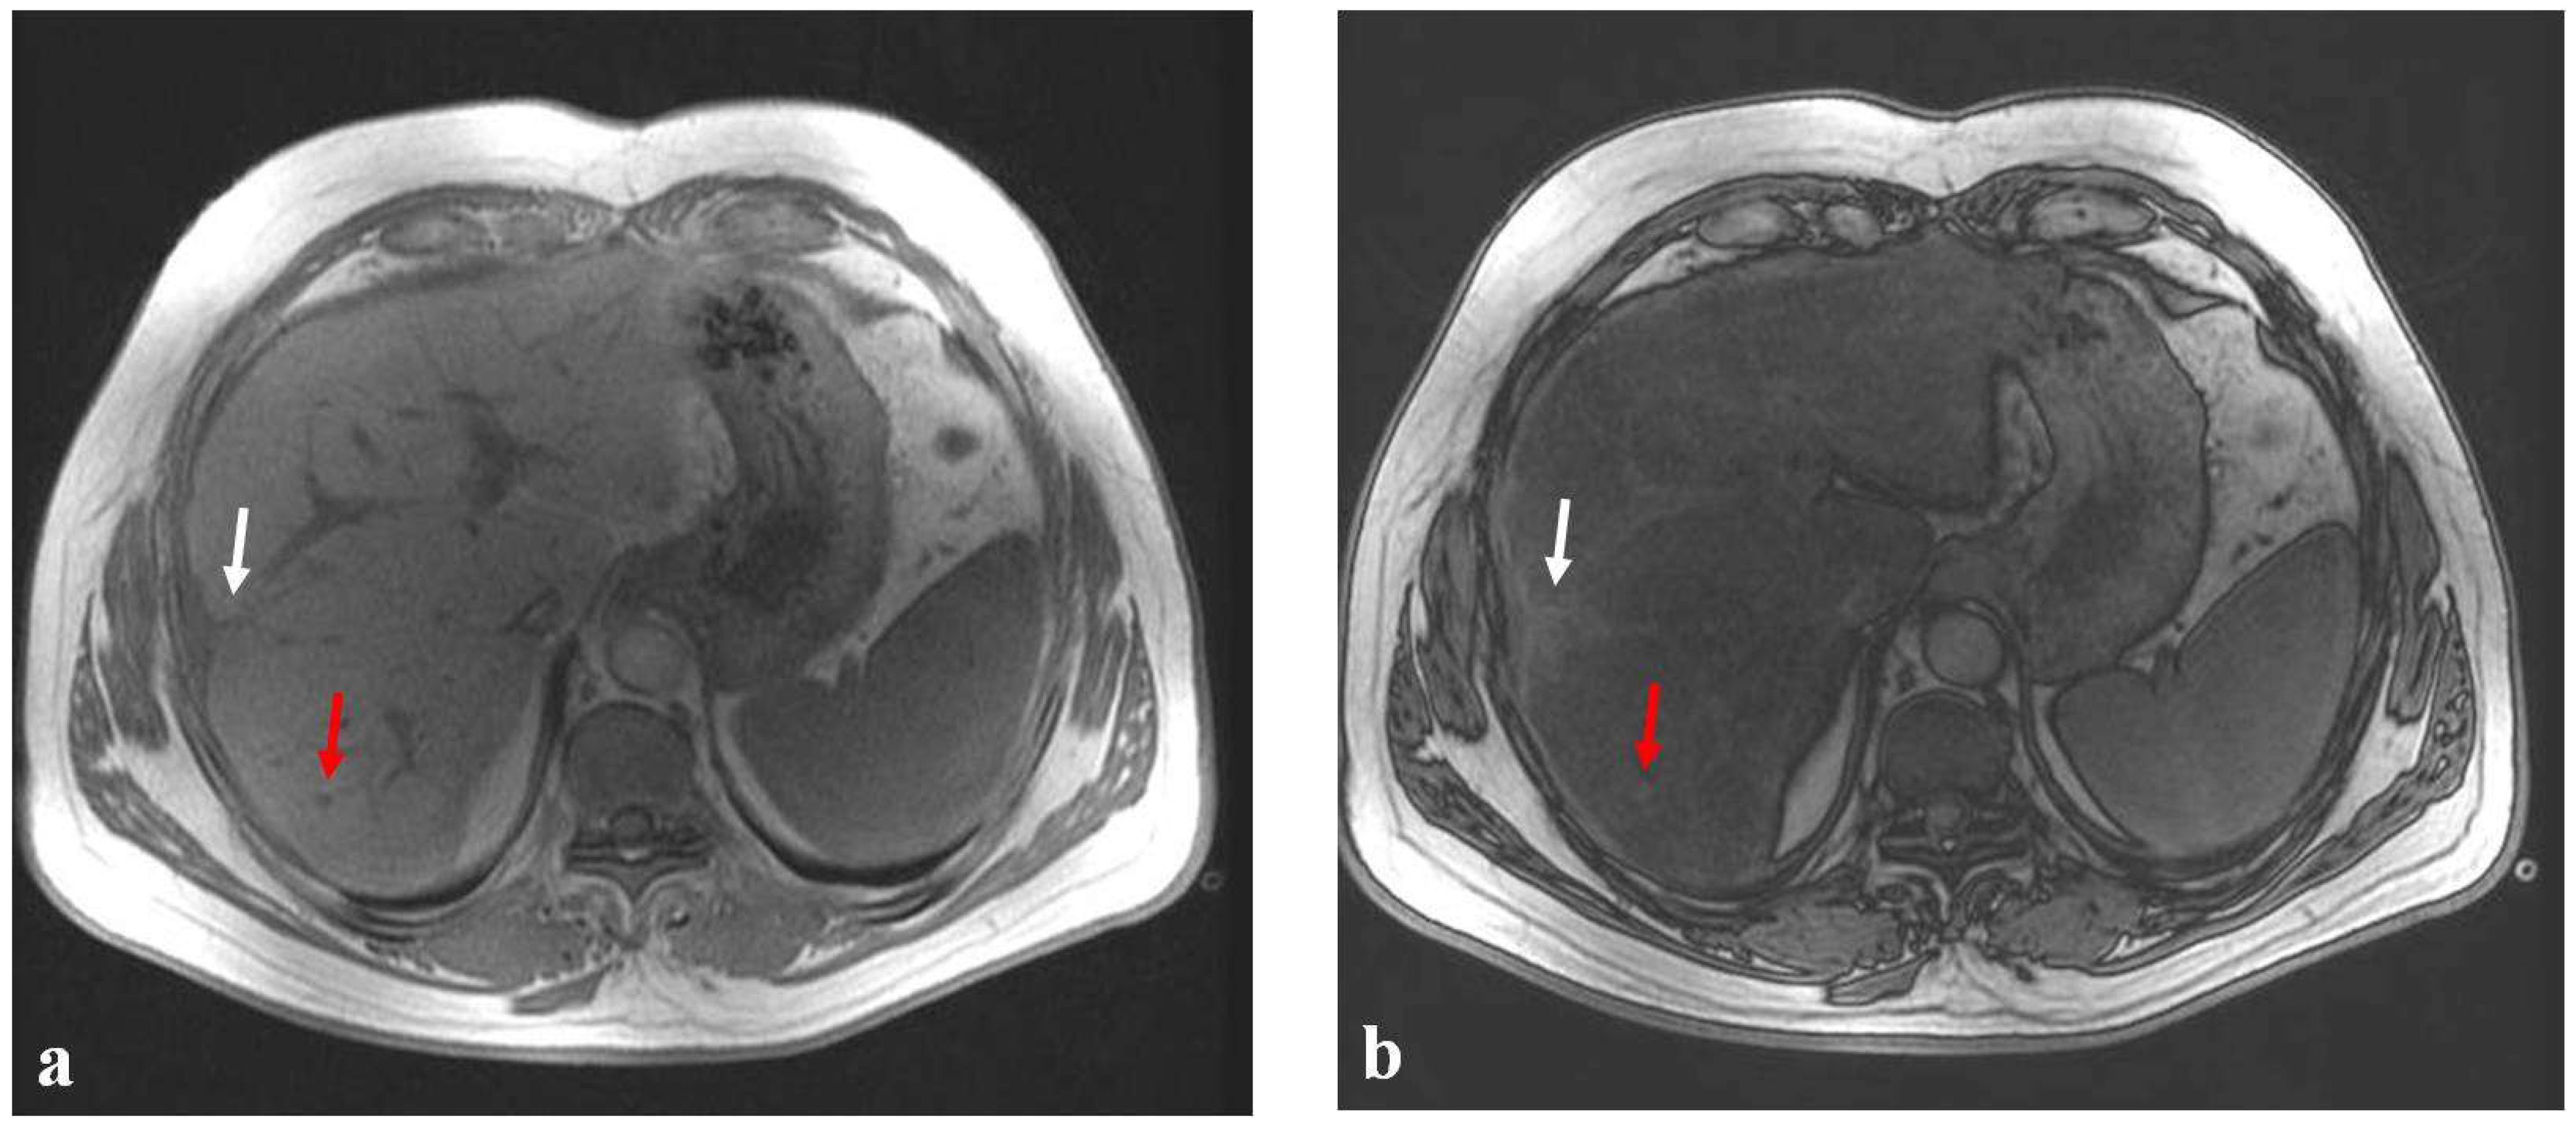

3. Sinusoidal Obstruction Syndrome (SOS)

- Zhang, Y.; Yan, Y.; Song, B. Noninvasive imaging diagnosis of sinusoidal obstruction syndrome: A pictorial review. Insights Imaging 2019, 10, 110. [Google Scholar] [CrossRef] [PubMed]

- Cayet, S.; Pasco, J.; Dujardin, F.; Besson, M.; Orain, I.; De Muret, A.; Miquelestorena-Standley, E.; Thiery, J.; Genet, T.; Le Bayon, A.G. Diagnostic performance of contrast-enhanced CT-scan in sinusoidal obstruction syndrome induced by chemotherapy of colorectal liver metastases: Radio-pathological correlation. Eur. J. Radiol. 2017, 94, 180–190. [Google Scholar] [CrossRef] [PubMed]

- Han, N.Y.; Park, B.J.; Yang, K.S.; Kim, M.J.; Sung, D.J.; Sim, K.C.; Cho, S.B. Hepatic Parenchymal Heterogeneity as a Marker for Oxaliplatin-Induced Sinusoidal Obstruction Syndrome: Correlation With Treatment Response of Colorectal Cancer Liver Metastases. AJR Am. J. Roentgenol. 2017, 209, 1039–1045. [Google Scholar] [CrossRef]

- Zhou, H.; Wang, Y.J.; Lou, H.; Xu, X.; Zhang, M. Hepatic sinusoidal obstruction syndrome caused by herbal medicine: CT and MRI Features. Korean J. Radiol. 2014, 15, 218–225. [Google Scholar] [CrossRef] [PubMed]

- Furlan, A.; Minervini, M.I.; Borhani, A.A.; Dioguardi Burgio, M.; Tublin, M.E.; Brancatelli, G. Hepatic sinusoidal dilatation: A review of causes with imaging-pathologic correlation. Semin. Ultrasound CT MR 2016, 37, 525–532. [Google Scholar] [CrossRef]

- Brancatelli, G.; Furlan, A.; Calandra, A.; Burgio, M.D. Hepatic sinusoidal dilatation. Abdom. Radiol. 2018, 43, 2011–2022. [Google Scholar] [CrossRef]